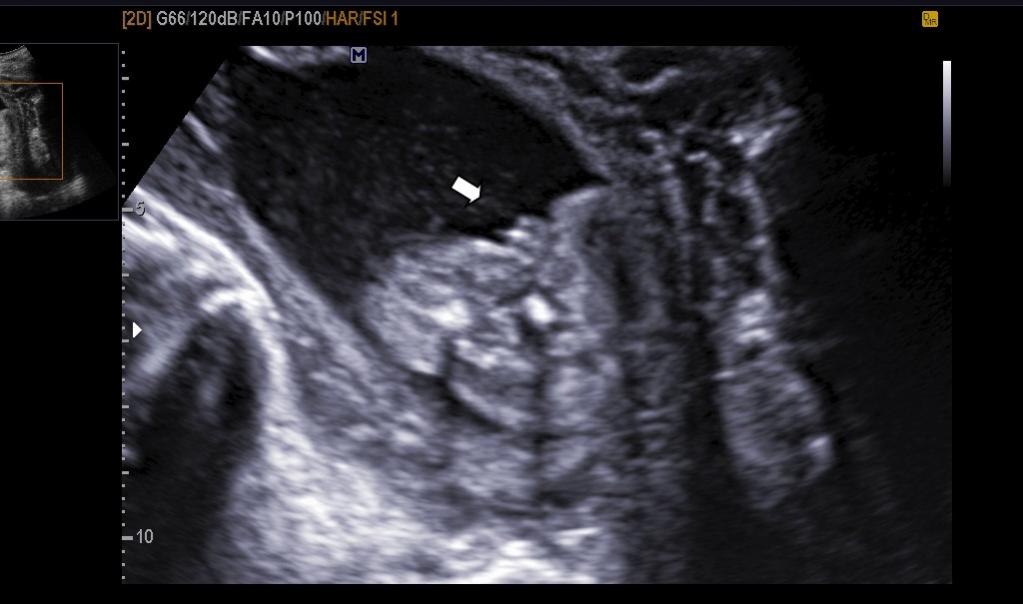

hi, these were taken at 17+1 day. I think i know but just want some second opinions. thanks. have added some more from the dvd too (photo's 4 and 5. do these photo's show girl bits????)

Looks very girly.

definate girl!!!

Definately a girl hun!!

Girl!

Definitely a girl!! I have 3 girls, and they all look just like this one!! Congratulations!

Yes a girl for sure! Congratulations!!